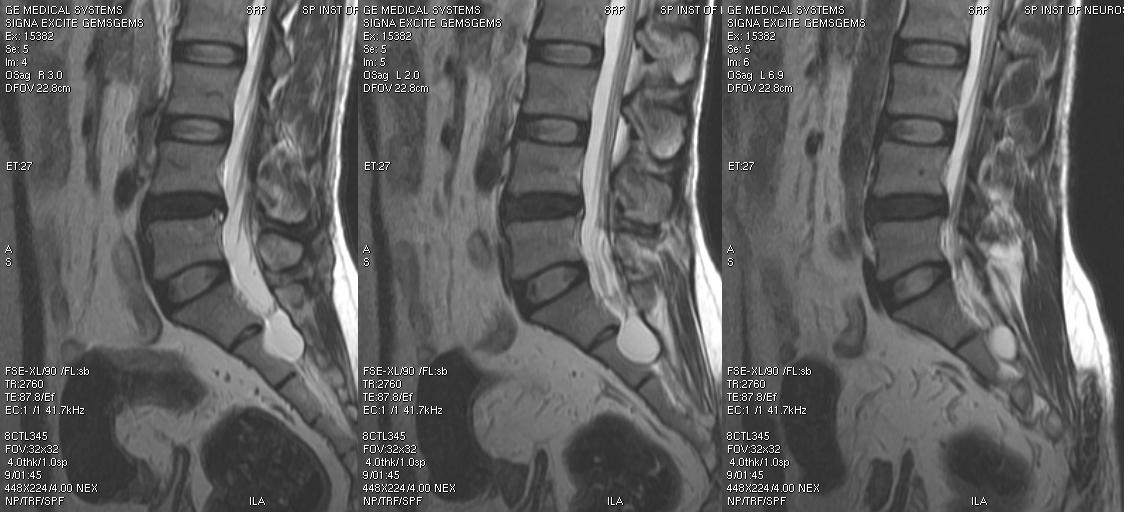

Врачи отмечают, что появление кисты в пояснично-крестцовом отделе позвоночника может быть связано с различными факторами, включая дегенеративные изменения, травмы или воспалительные процессы. Специалисты подчеркивают, что такие кисты часто не проявляют себя симптоматически, однако в некоторых случаях могут вызывать боль, дискомфорт и ограничение подвижности. Важно, чтобы пациенты не игнорировали признаки, такие как онемение или слабость в конечностях, так как это может указывать на сдавление нервных корешков. Врачи рекомендуют регулярные обследования и, при необходимости, проведение магнитно-резонансной томографии для точной диагностики. Лечение может варьироваться от наблюдения до хирургического вмешательства, в зависимости от размера кисты и степени ее воздействия на здоровье пациента.

- МРТ головного и спинного мозга.